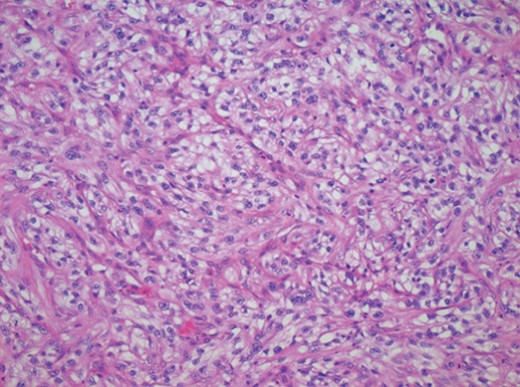

An initial biopsy however showed features consistent with a metastatic adenocarcinoma consistent with the previously removed RCC (see Fig. 2).

Photomicrograph of a specimen from the lower lip demonstrating the presence of RCC cells.